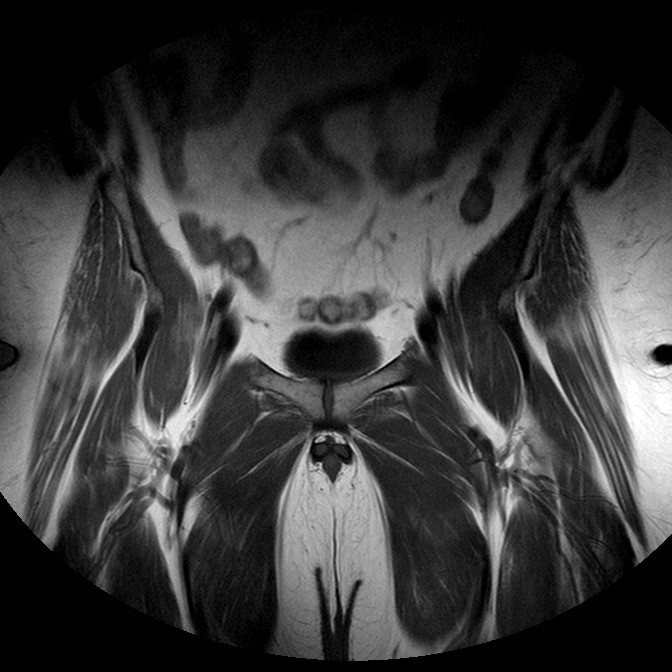

Esami: RMN BACINO

T1w TSE

Evidenti e simmetriche alterazioni osteofitosiche in regione coxo femorale con riduzione delle rime articolari. Degenerazione completa del cercine glenoideo. Non attuali segni di versamento articolare. Non segni di edema osseo che escludono attuale algodistrofia od osteonecrosi. Lieve e simmetrica riduzione del trofismo della muscolatura glutea.